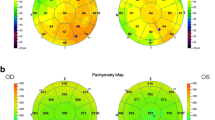

AS-OCT in the diagnosis and assessment of therapy in dry eye

It is only in the past 2 years that AS-OCT has emerged as a quick, non-invasive, and quantitative diagnostic tool in the assessment of dry eye disease, particularly ADDE [212]. In the assessment of DED, tear film biometry is of particular interest. The measurements taken include the tear meniscus height (TMH), the tear meniscus depth (TMD), and tear meniscus area (TMA) [212, 221]. These parameters are significantly decreased in patients with dry eye disease, especially secondary to Sjögren’s syndrome, as compared to controls (Fig. 2), thereby serving as reliable, accurate, non-invasive, and quick diagnostic markers of Sjögren’s disease in the evaluation of DED [212, 222]. Based on stronger correlation with other ocular surface tests, the lower tear menisci measurements seem to be more clinically relevant than upper menisci in the diagnosis of dry eye [223]. Ibrahim et al. showed that TMH, with a sensitivity and specificity of 67 % and 81 % respectively, is reduced in dry eye disease, along with other tests measuring the tear film such as TMH on slit-lamp examination, tear meniscometry, tear break-up time, and Schirmer’s test [212]. Furthermore, they proceeded to test the role of OCT-derived TMH measurements in assessing response to punctal plug therapy for dry eye, which confirmed TMH as a quick and sensitive parameter in the diagnosis and therapeutic assessment of dry eye [224]. Other groups have confirmed the correlation of AS-OCT tear film biometry with Schirmer’s test [225], while retaining high reliability of central tear film measurements (intraclass correlation coefficient = 0.97), making AS-OCT a reliable, precise and accurate tool in tear film biometry [226]. However, it is worthwhile to note that tear film biometry may not be useful in the assessment of MGD-dependent EDE.

Further, Chen et al. found that tear meniscus volume measurements using AS-OCT are reduced in Sjögren’s patients, correlating strongly with corneal staining and TBUT [227]. It has been determined that OCT-derived tear menisci measurements are most useful in diagnosing and following patients with Sjögren’s syndrome-related dry eye than patients with non-Sjögren’s dry eye or evaporative dry eye [221]. Dry eye symptoms may also be associated with conjunctivochalasis. Several groups have successfully adapted OCT-derived tear menisci measurements to evaluate and classify these lid-parallel conjunctival folds toward developing further objective parameters in the assessment of DED [211, 228, 229].